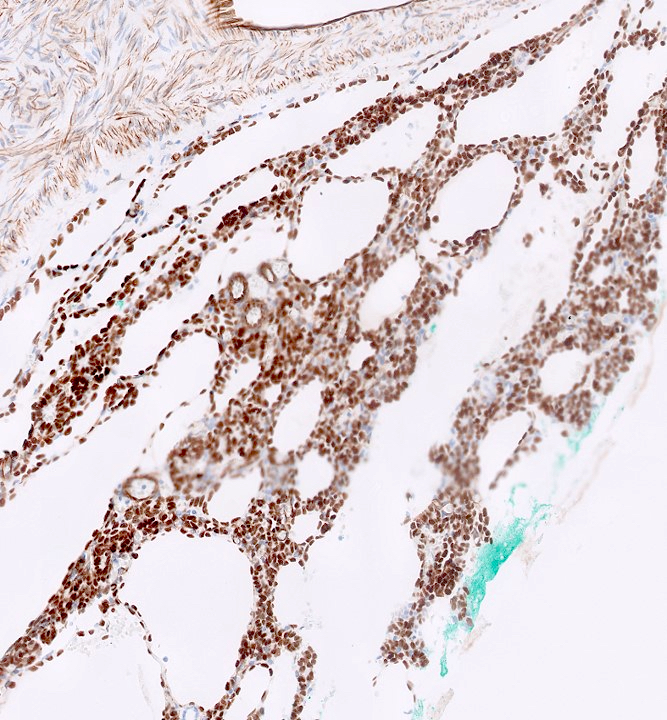

Microscopic (histologic) description

- Cysts lined with flat / cuboidal / hobnail cells (or are denuded)

- Epithelial elements consist mainly of mature and immature / abortive tubules and small papillae resembling immature glomeruli

- Key histological findings of the variably cellular septa include

- Nephroblastomatous epithelial elements

- Islands of undifferentiated blastema and differentiated mesenchymal elements (skeletal muscle and less often cartilage and fat) (J Urol 2010;183:1585)

- Focally, the septal elements may protrude into the cystic spaces in microscopic papillary folds

Microscopic (histologic) images

Contributed by Americo Brilhante, M.D. and Daniel Athanazio, M.D., Ph.D.

Positive stains

- WT1: blastemal cells (J Cancer Res Ther 2022;18:209)